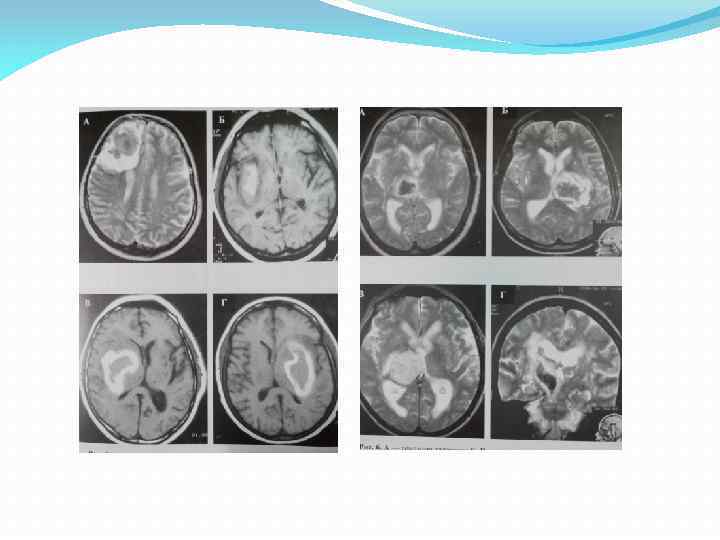

Гематома путаменально капсулярного типа. Операция – удаление гематомы пункционно аспирационным способом Гематома путаменально капсулярного типа. Операция – удаление гематомы пункционно аспирационным способом

Гематома путаменально капсулярного типа. Операция – пункционное удаление гематомы, дополненное локальным фибринолизом Гематома путаменально капсулярного типа. Операция – пункционное удаление гематомы, дополненное локальным фибринолизом